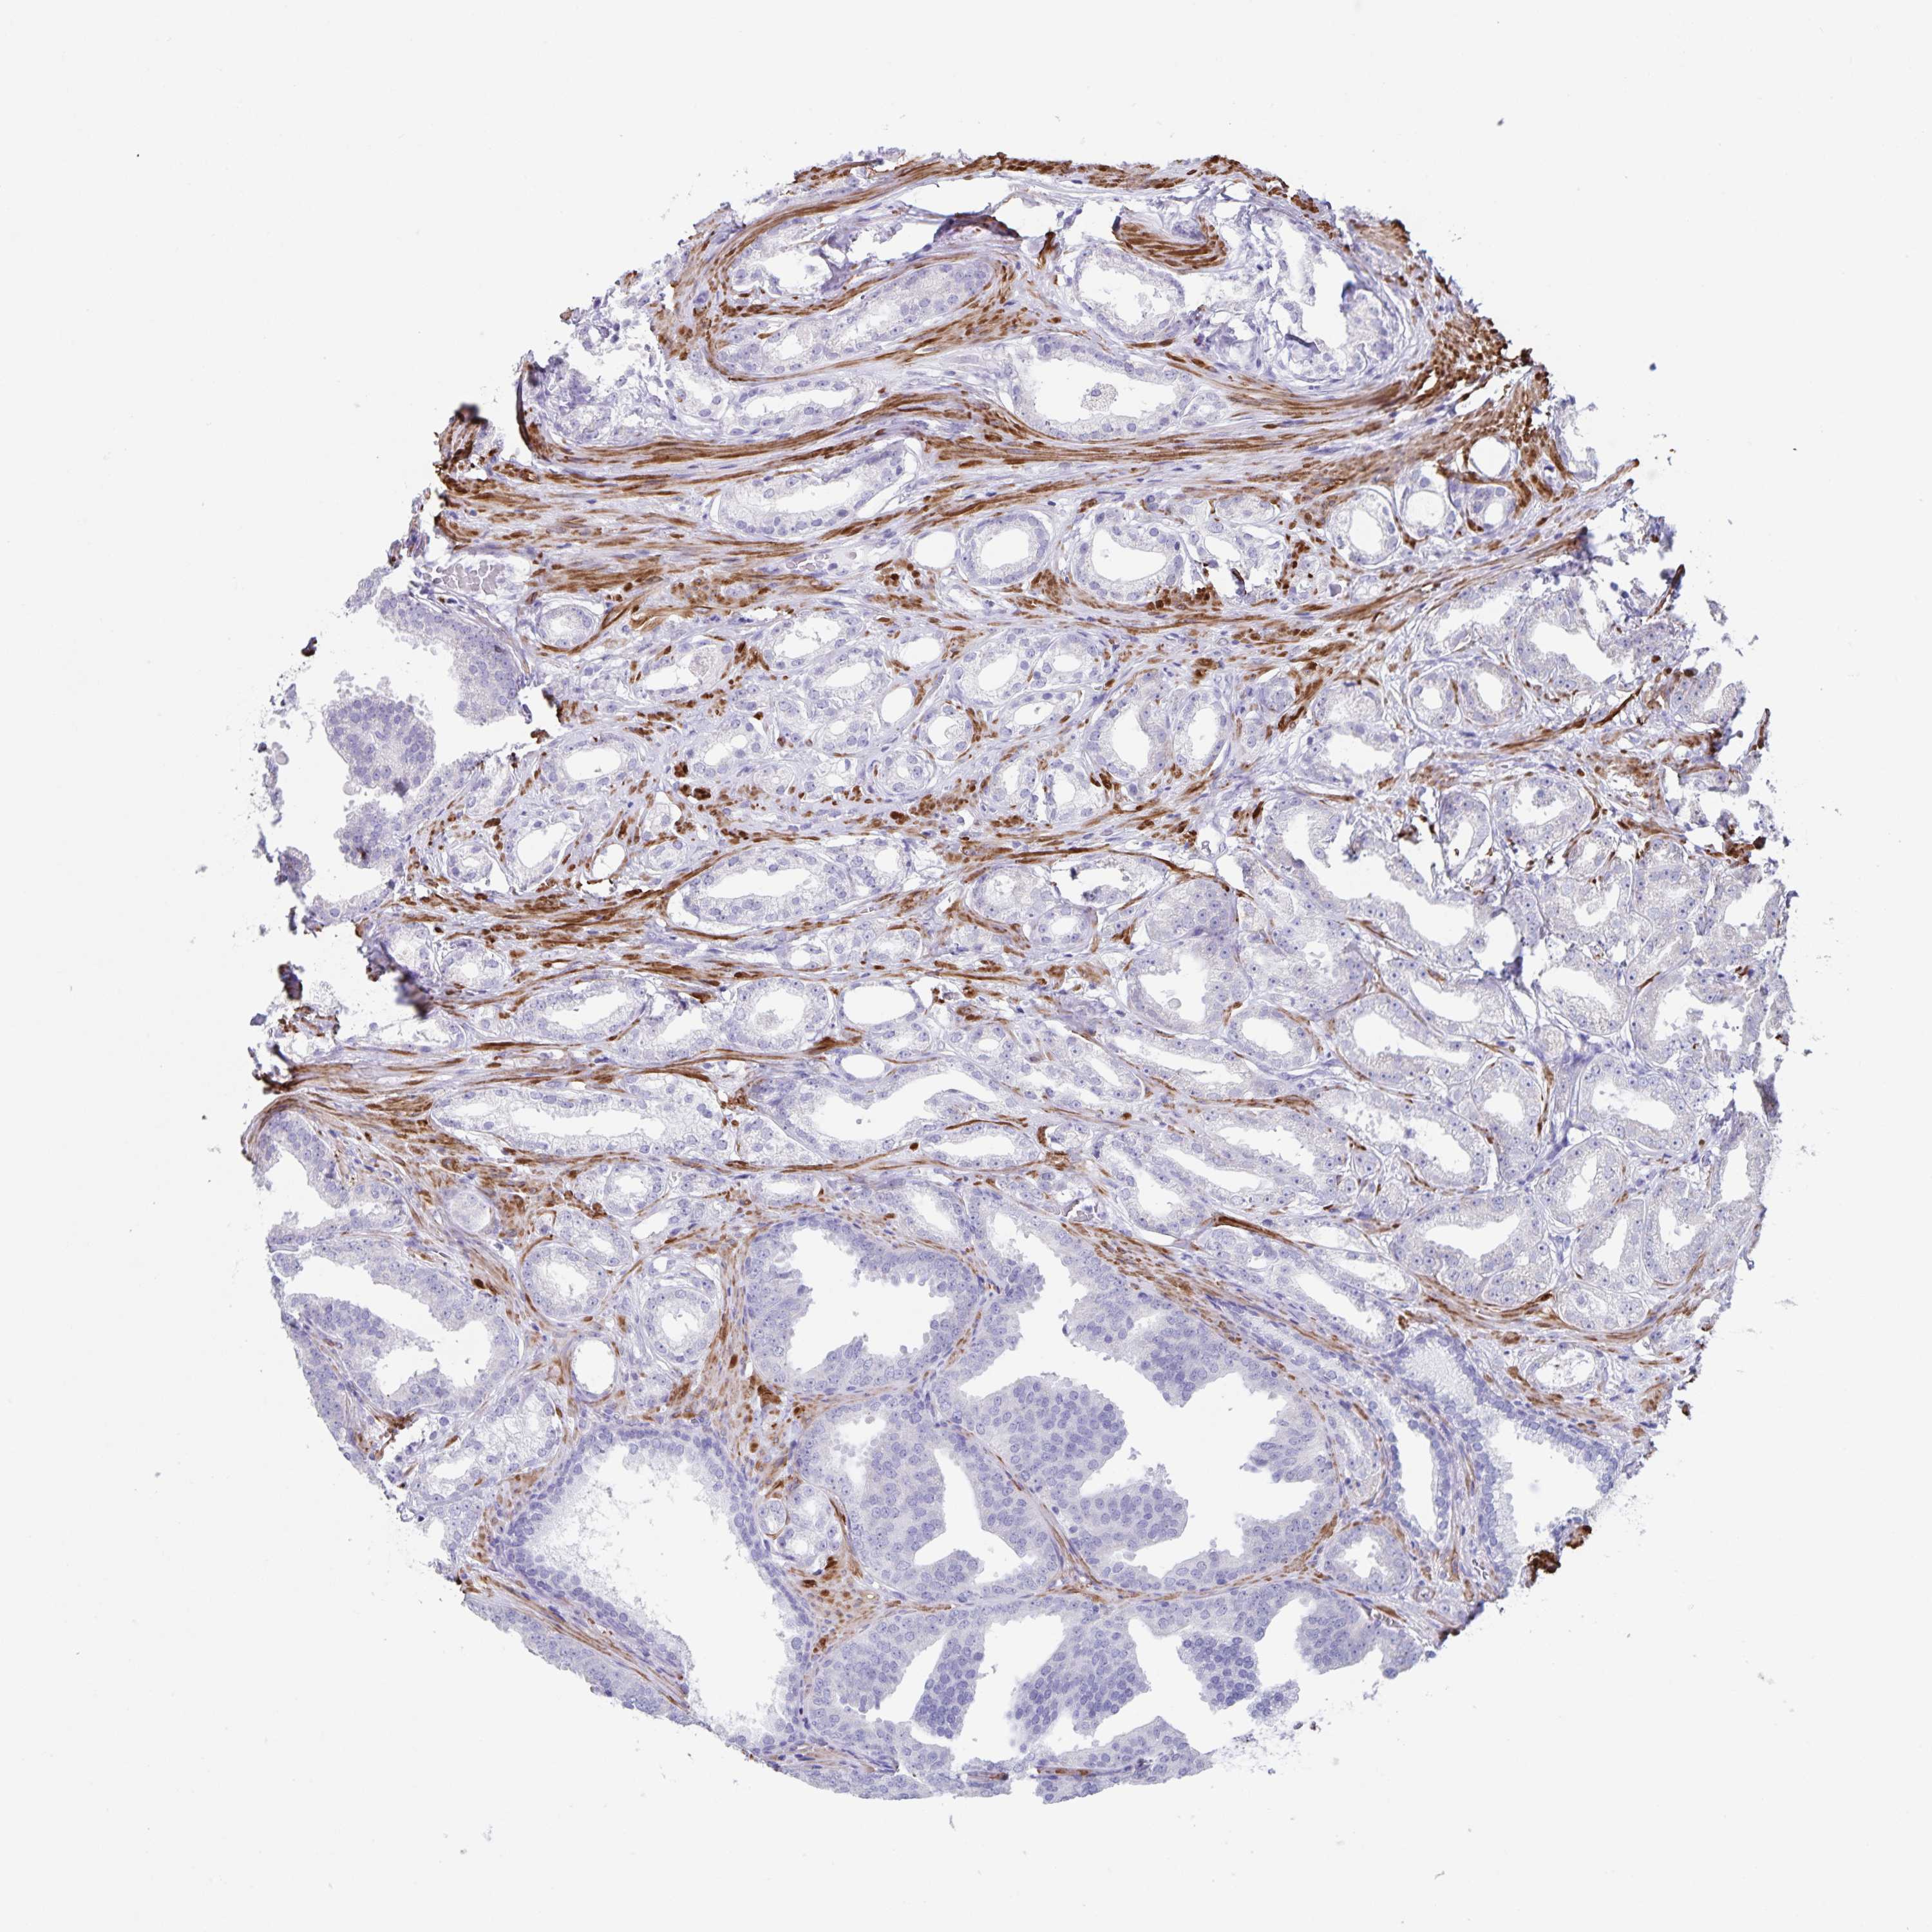

PROSTATE CANCER - Protein expressioni

A mouse-over function shows sample information and annotation data. Click on an image to view it in a full screen mode. Samples can be filtered based on level of antibody staining by selecting one or several of the following categories: high, medium, low and not detected. The assay and annotation is described here.

Note that samples used for immunohistochemistry by the Human Protein Atlas do not correspond to samples in the TCGA dataset.

Antibody stainingi

Antibody staining in the annotated cell types in the current human tissue is reported as not detected, low, medium, or high, based on conventional immunohistochemistry profiling in selected tissues. This score is based on the combination of the staining intensity and fraction of stained cells.

Each image is clickable and will lead to virtual microscopy that enables deeper exploration of all samples and also displays staining intensity scores, fraction scores and subcellular localization as well as patient and tissue information for each sample.

Antibody HPA040066

Antibody HPA044200

Antibody CAB017192

Staining

High

Medium

Low

Not detected

Intensity

Strong

Moderate

Weak

Negative

Quantity

>75%

75%-25%

<25%

None

Location

Nuclear

Cytoplasmic/membranous

Cytoplasmic/membranous,nuclear

Adenocarcinoma, High grade

Adenocarcinoma, Medium grade

Adenocarcinoma, Low grade